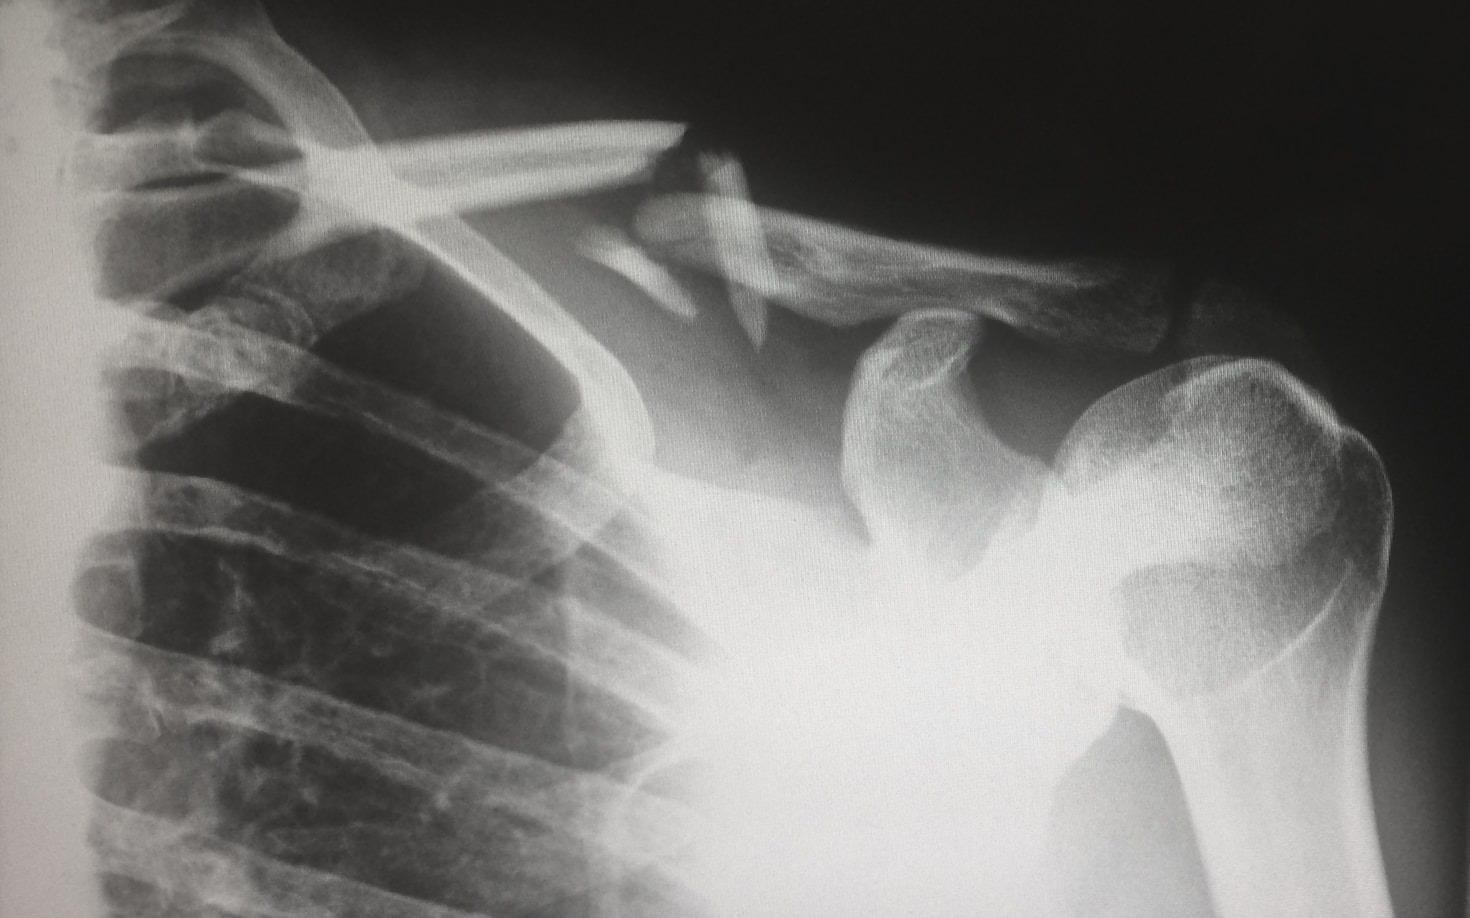

A área da radiologia está em constante evolução. Novas técnicas, novos equipamentos e o impacto da automação em todos os setores alicerçados pelo uso da inteligência artificial obriga os profissionais dessa área a estarem preparados para os desafios que se apresentam. Educação contínua é a palavra de ordem. Todo conhecimento atualizado é o que vai…